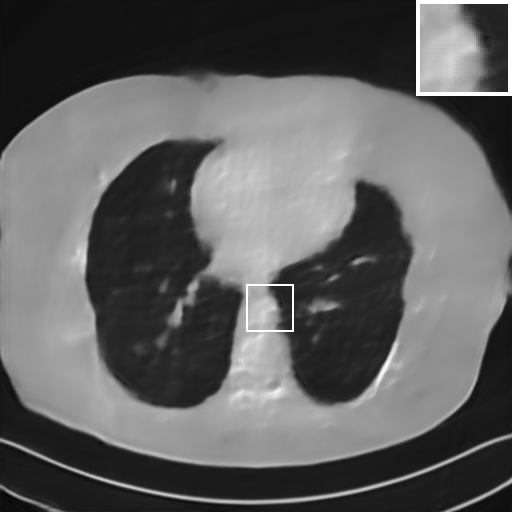

Fig. 4 presents the reconstruction results and residual images obtained by different methods for limited-angle reconstruction. As can be seen, the learning-based methods outperform the direct method and TV model, which exhibit serious artifacts in the missing angle region. Although the denoiser introduced by the FBP-Unet can somehow deal with the noises, the result still presents obvious artifacts. Compared to the SIPID, PD-net and FSR-nets, our LRIP-net1/2 can better preserve the image details and edges with less information left in the residual images. Thus, both the quantitative and qualitative results confirm that the low-to-high double-resolution strategy can improve the reconstruction accuracy for the limited-angle reconstruction problem.

We observe that the low-resolution image prior plays an important role in our method. More specifically, we compare the results of our LRIP-net with respect to different low-resolution priors, which are obtained by down-sampling rate of 1/2, 1/4, and 1/8, respectively. As can be seen in Table III, the best reconstruction results are obtained with the image prior reconstructed by the down-sampling rate of for 150∘, 120∘ and 90∘ limited-angle reconstruction. The visual comparison based on different image priors are also provided in Fig. 5, where obviously less artifacts are left in the reconstruction image by LRIP-net1/8. By comparing the running time, it is easy to see that the smaller the low-resolution image prior, the faster the LRIP-net works.